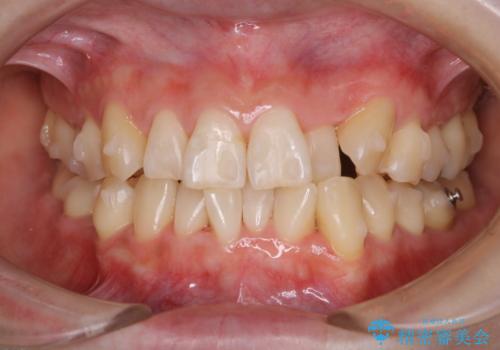

ワイヤー矯正中に歯の染め出し

担当医 歯科衛生士